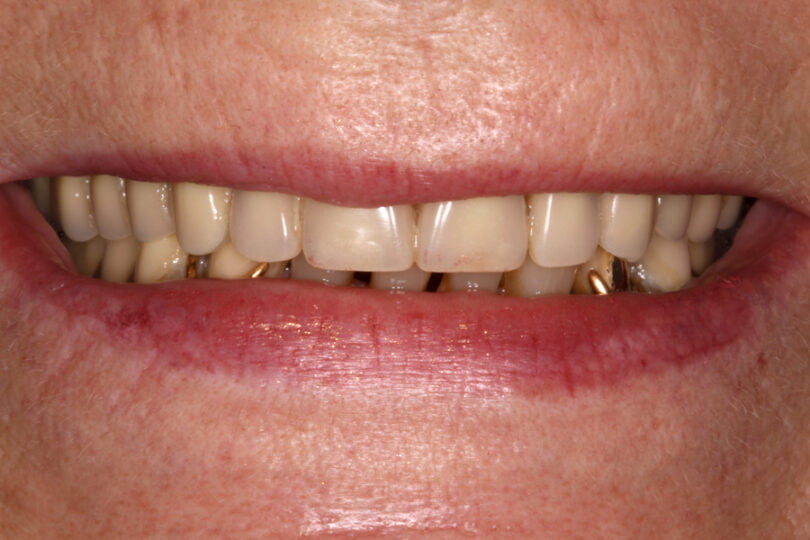

Quatro dos seis implantes foram de 5,5 mm de comprimento por 5 mm de diâmetro, um implante foi de 6,5 mm de comprimento por 3,75 mm de diâmetro e o último implante foi de 6,5 mm de comprimento por 5 mm de diâmetro (figura 2).

As seguintes imagens apresentam um dos casos incluídos no estudo (figura 03 – 15).